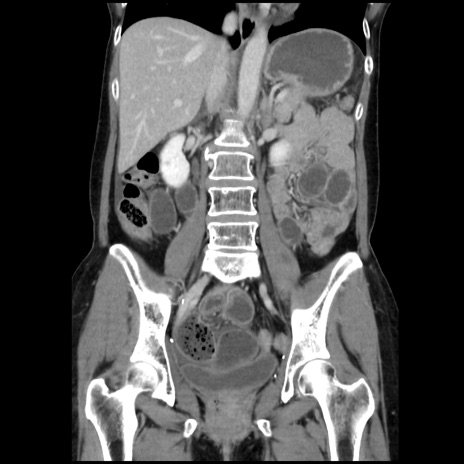

症例32(冠状断像)

【症例】40歳代 女性

【主訴】上腹部痛、嘔気・嘔吐

【現病歴】約9時間前頃から急に上腹部痛、嘔気、嘔吐が出現。改善しないため救急要請。

【既往歴】子宮頚癌(広汎子宮全摘術、放射線療法)、腸閉塞

【身体所見】腹部:平坦、軟、腸雑音亢進、上腹部を中心に腹部全体に圧痛あり。

【データ】WBC 8400、CRP 0.03